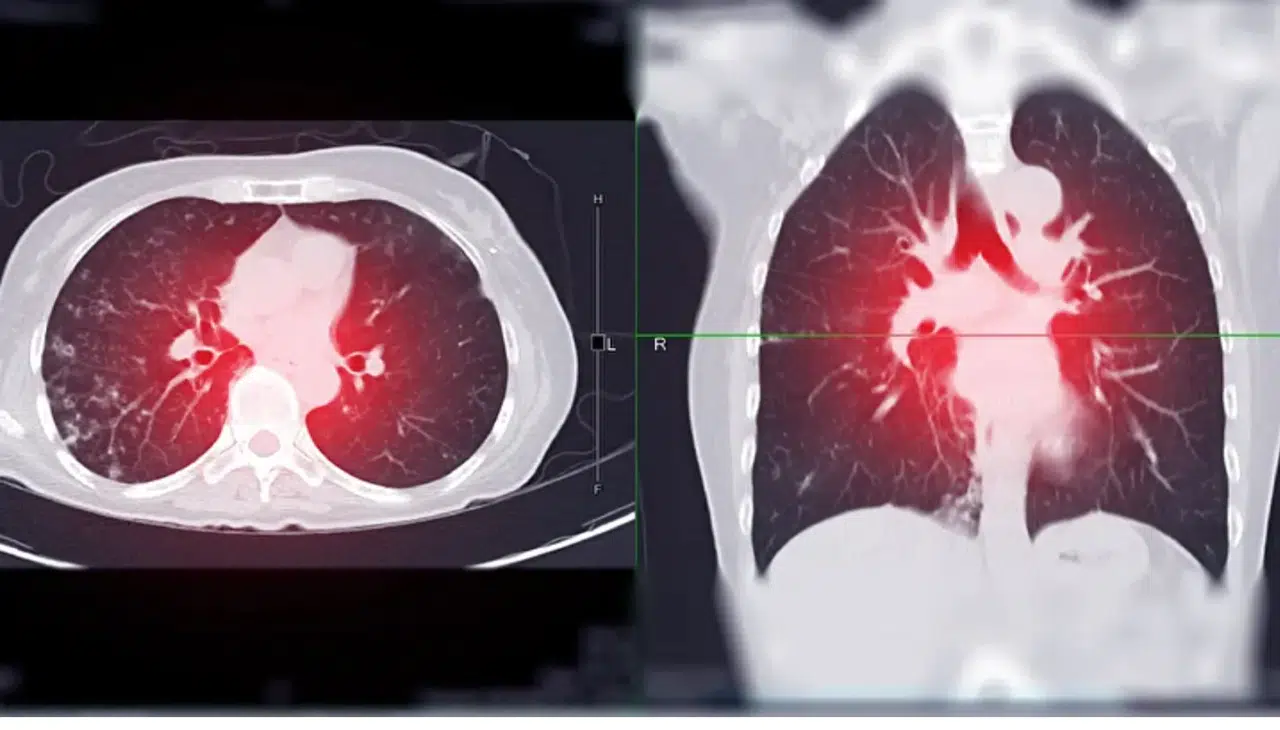

Uzmanlar, özellikle 50 ile 80 yaş arasındaki, uzun yıllar sigara kullanmış bireylerin düşük doz bilgisayarlı tomografi (BT) taramasına girmelerinin erken teşhis için hayati önem taşıdığını vurguluyor. Bu yöntemle erken evrede tespit edilen akciğer kanseri vakalarında sağkalım oranı yüzde 60 ile 90 arasında değişiyor.